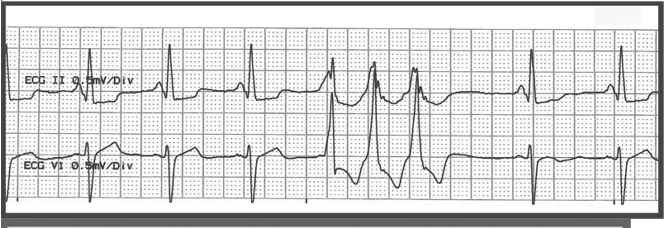

Premature Ventricular Contraction

BE SPECIFIC

Trigeminal PVC

Run or Burst PVC

Multifocal PVC